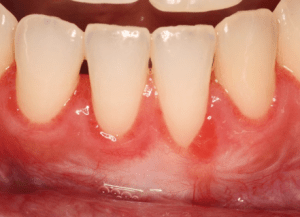

Before Connective Tissue Graft